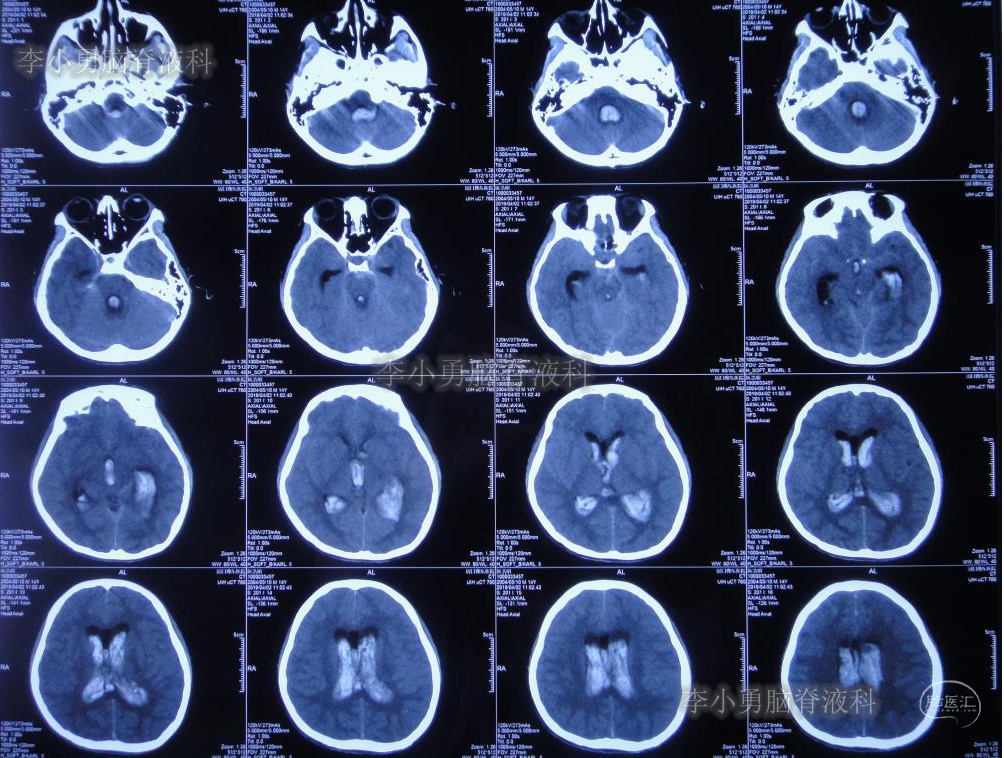

次日即2019年4月2日给予行腰椎穿刺术,引流出血性脑脊液;但腰椎穿刺术刚结束突然晕厥,再次复查头颅CT(图-4):脑室内出血量较前明显增多,四脑室及中央导水管铸形。

图-4:2019年4月2日头颅CT:脑室内积血明显增多

次日2019年4月3日(脑出血后8天),转至河南省郑州市某三甲医院;入院当日头颅CT(图-5)及CTA(图-6)检查结果:出血量较昨日无增加,动脉血管未见明显异常。

图-5:2019年4月3日头颅CT:出血量无增加